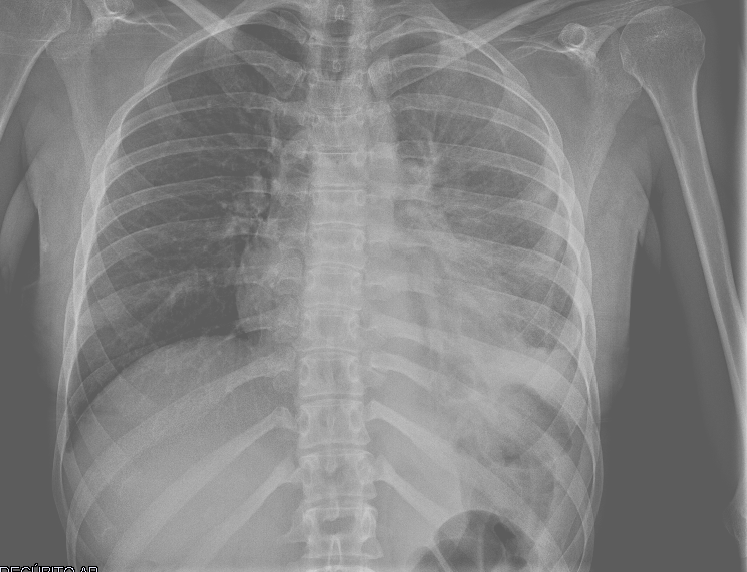

• Rx tórax AP en decúbito supino: Condensación pulmonar parahiliar y paracardíaca izquierda que borra la silueta cardiaca con derrame pleural asociado de menos de 1/3 de dicho hemitórax.